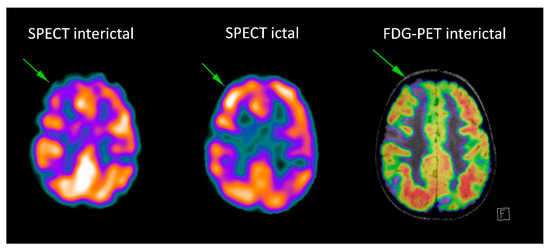

Figure 3.

Patient with tuberosis sclerosis complex: the interictal Single-photon emission computed tomography (SPECT) and fluorodeoxyglucose-positron emission tomography (FDG-PET) (fused with MRI FLAIR images) show multiple hypometabolic foci, corresponding to the multiple tubers. Ictal SPECT shows ictal hyperperfusion of the superior right frontal tuber.

Ictal SPECT with perfusion tracers is the only technique able to show the perfusion changes occurring during the epileptic event: two acquisitions are usually performed, in the ictal and interictal condition (as exemplified in Figure 3) and digital subtraction techniques are used to complement visual interpretation to identify the subtlest changes associated with the seizure.